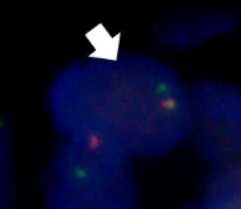

Break-apart fluorescent in situ hybridization (FISH) was then performed for the MAML2 and SS18 genes. MAML2 translocations have been implicated in the development of mucoepidermoid carcinomas whereas MSA is characterized by a gene fusion between SS18 and MEF2C. The SS18::MEF2C rearrangement is unique to MSA and was originally identified by RNA sequencing. Using a count of at least 100 cells and a 10% disruption threshold for gene rearrangement, the authors detected no disruption of the MAML2 gene (100% intact). On the other hand, they detected SS18 disruption in 60% of cells, which suggested SS18 translocation and a diagnosis of MSA.